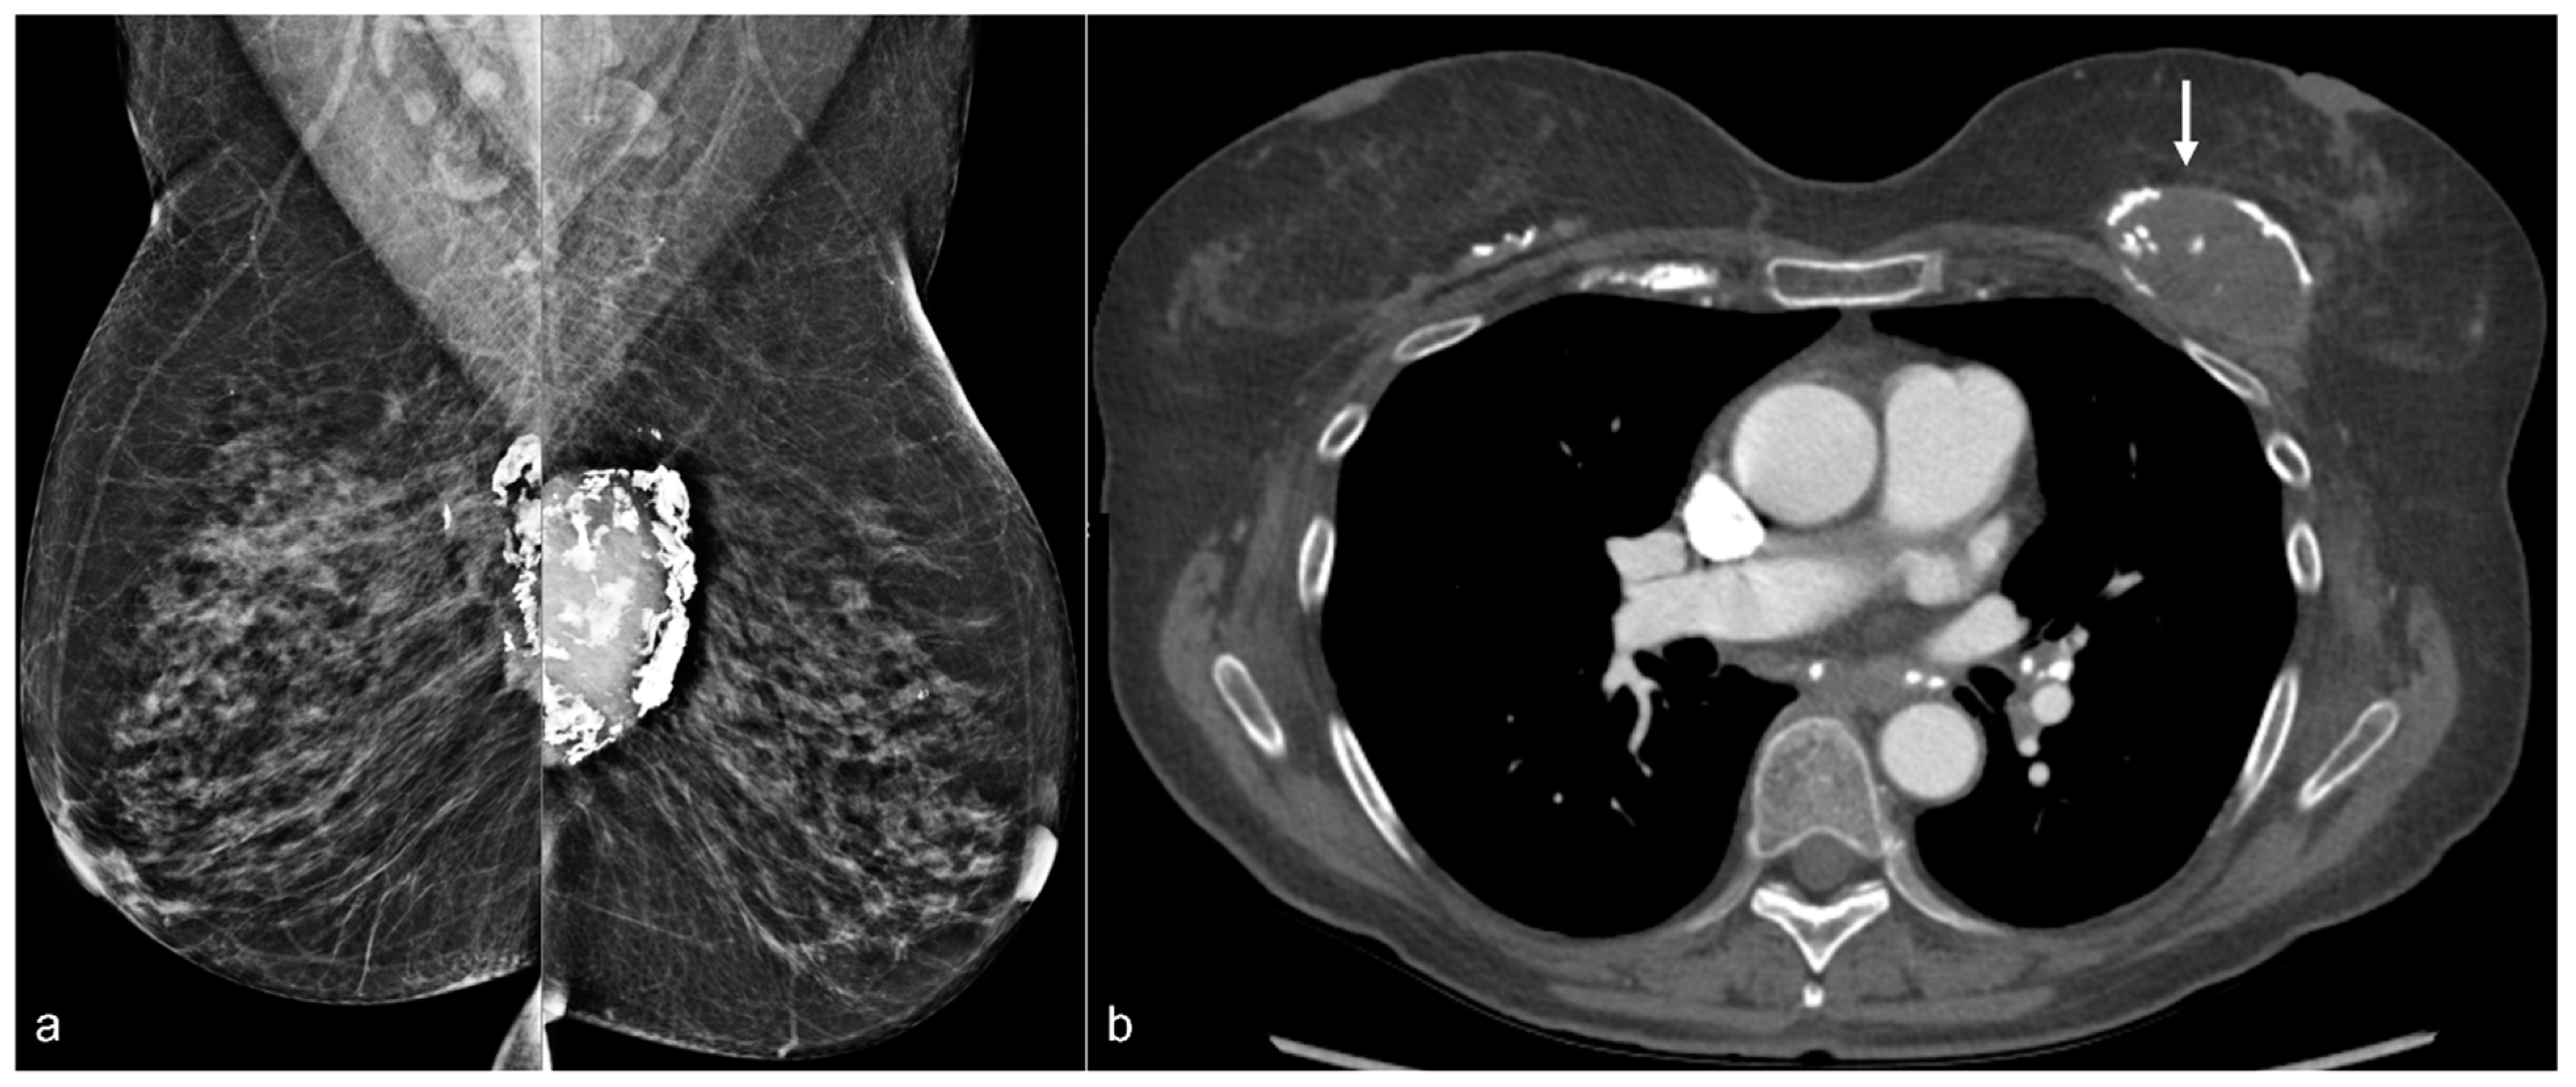

Figure 12. A 70-year-old patient’s mammogram (a) demonstrates bilateral calcified implant capsules with a dense mass in the left prepectoral location on the MLO view. CT (b) confirms a left breast seroma (arrow) with fibrous capsular calcifications.